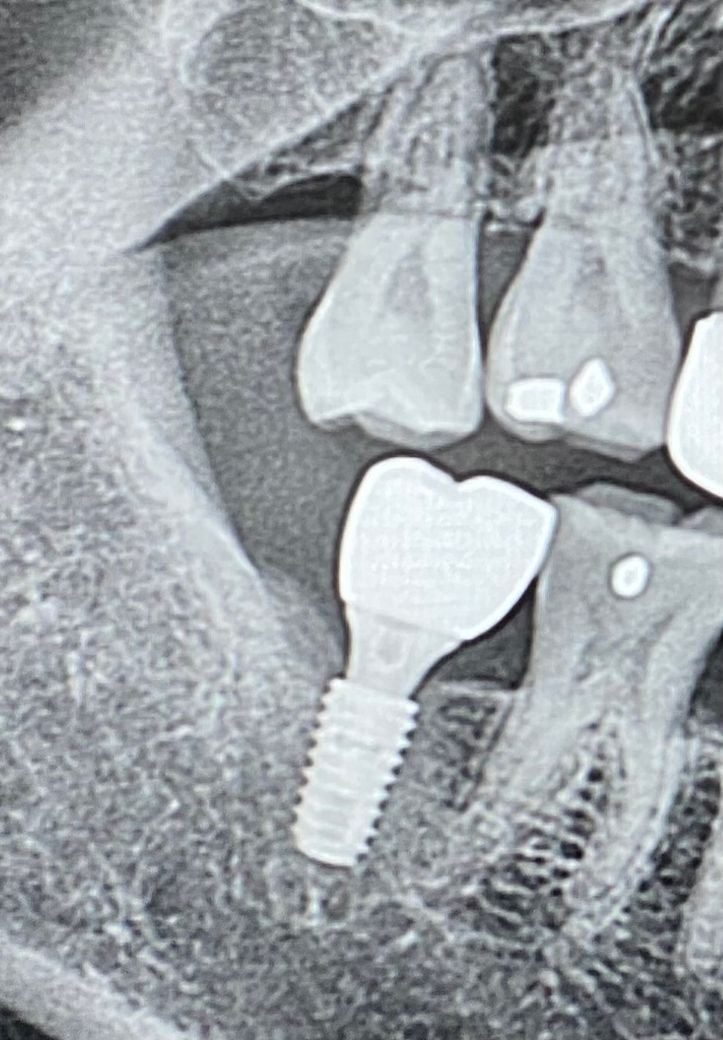

사진 치료 전후사진 첨부 드려요

• 1번 째 사진

위쪽치아가 많이 내려와보입니다. 정확한 상태를 알수는 없으나 위쪽. 치아를 건드려야 할 것 같습니다.

엑스레이 상으로는 크게 문제가 되는건 없는거 같습니다. 사진상으로 보면 임플란트 하는동안에 대합되는 치아가 약간 정출된거 같으니 교합조정을 다시 받아보시는게 좋을것같습니다.